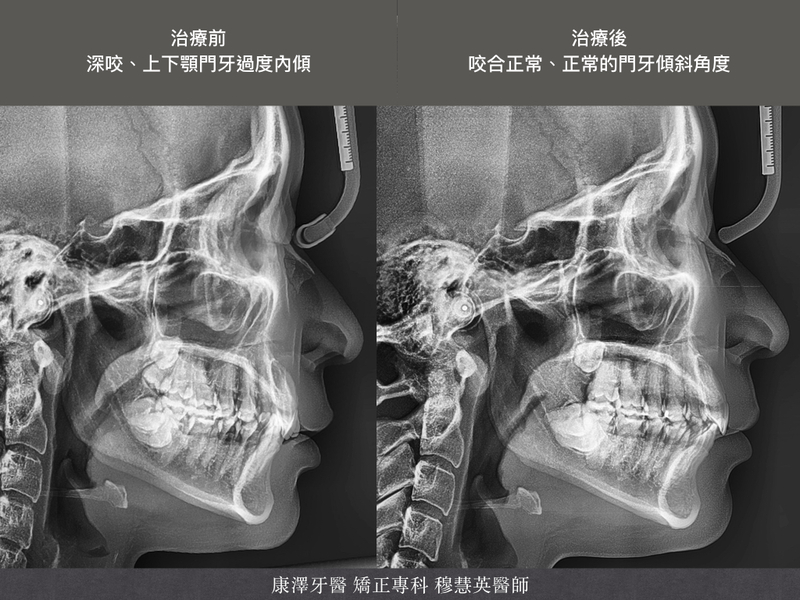

從深咬與門牙內傾到完美咬合:隱適美+骨釘矯正案例

在齒顎矯正中,安格氏二類二級(Class II Division 2) 是較具挑戰性的咬合問題,典型特徵包括上顎門牙內傾、深咬與齒列擁擠,會影響美觀與咬合功能。本案例患者透過隱適美透明牙套+骨釘輔助矯正,成功改善牙齒排列與深咬問題,使門牙恢復正常角度、改善深咬,打造自然和諧的微笑。

矯正成果:自然的笑容與穩定的咬合

✨ 門牙內傾改善,微笑更自然

✨ 深咬大幅改善,咬合穩定

✨ 齒列整齊,牙弓型態更理想

✨ 下顎活動度提升,降低顳顎關節壓力